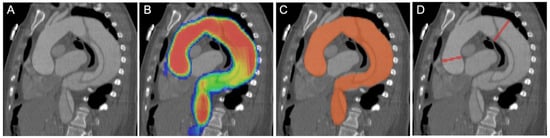

Figure 6 illustrates a sample case of accurate AI-based aortic segmentation even in a non-enhanced scan of a patient with a history of open surgical aortic repair and chronic dissection.

Figure 6. Seventy-two-year-old woman with a medical history of open surgical repair of ascending aortic aneurysm with graft placement and development of chronic dissection. (A) Non-enhanced scan as basis for (B) aortic borderline (red line) detection by the algorithm demonstrating accurate segmentation of the aorta including both the true and false lumen. (C) Contrast-enhanced scan with visible aortic dissection and dilation.